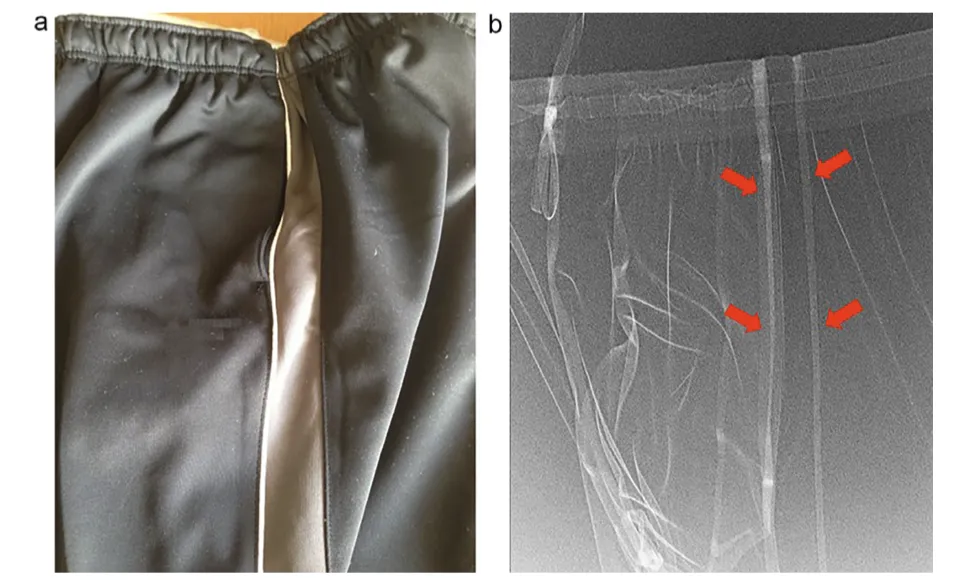

前文第一案例中的運動褲,箭頭對着褲子裏含有金屬纖維部分 圖源:文獻

MRI使用強大的磁場和射頻脈衝來生成人體內部的圖像。當銀質纖維暴露在MRI的高頻電磁場中時,會在金屬纖維內感應出渦流。這些渦流是因電磁感應產生的,它們在金屬內部循環,導致電流集中在某些區域,特別是纖維接縫或金屬成分較集中的部位。

銀是一種高導電性的金屬,因此即使是微小的渦流也能產生顯著的熱量。加上,銀質纖維在衣物中的分佈容易形成閉環,會使渦流效應更加顯著。當這些熱量無法迅速散開時,就會在接觸皮膚的地方積聚,導致局部温度升高,從而引發灼傷。